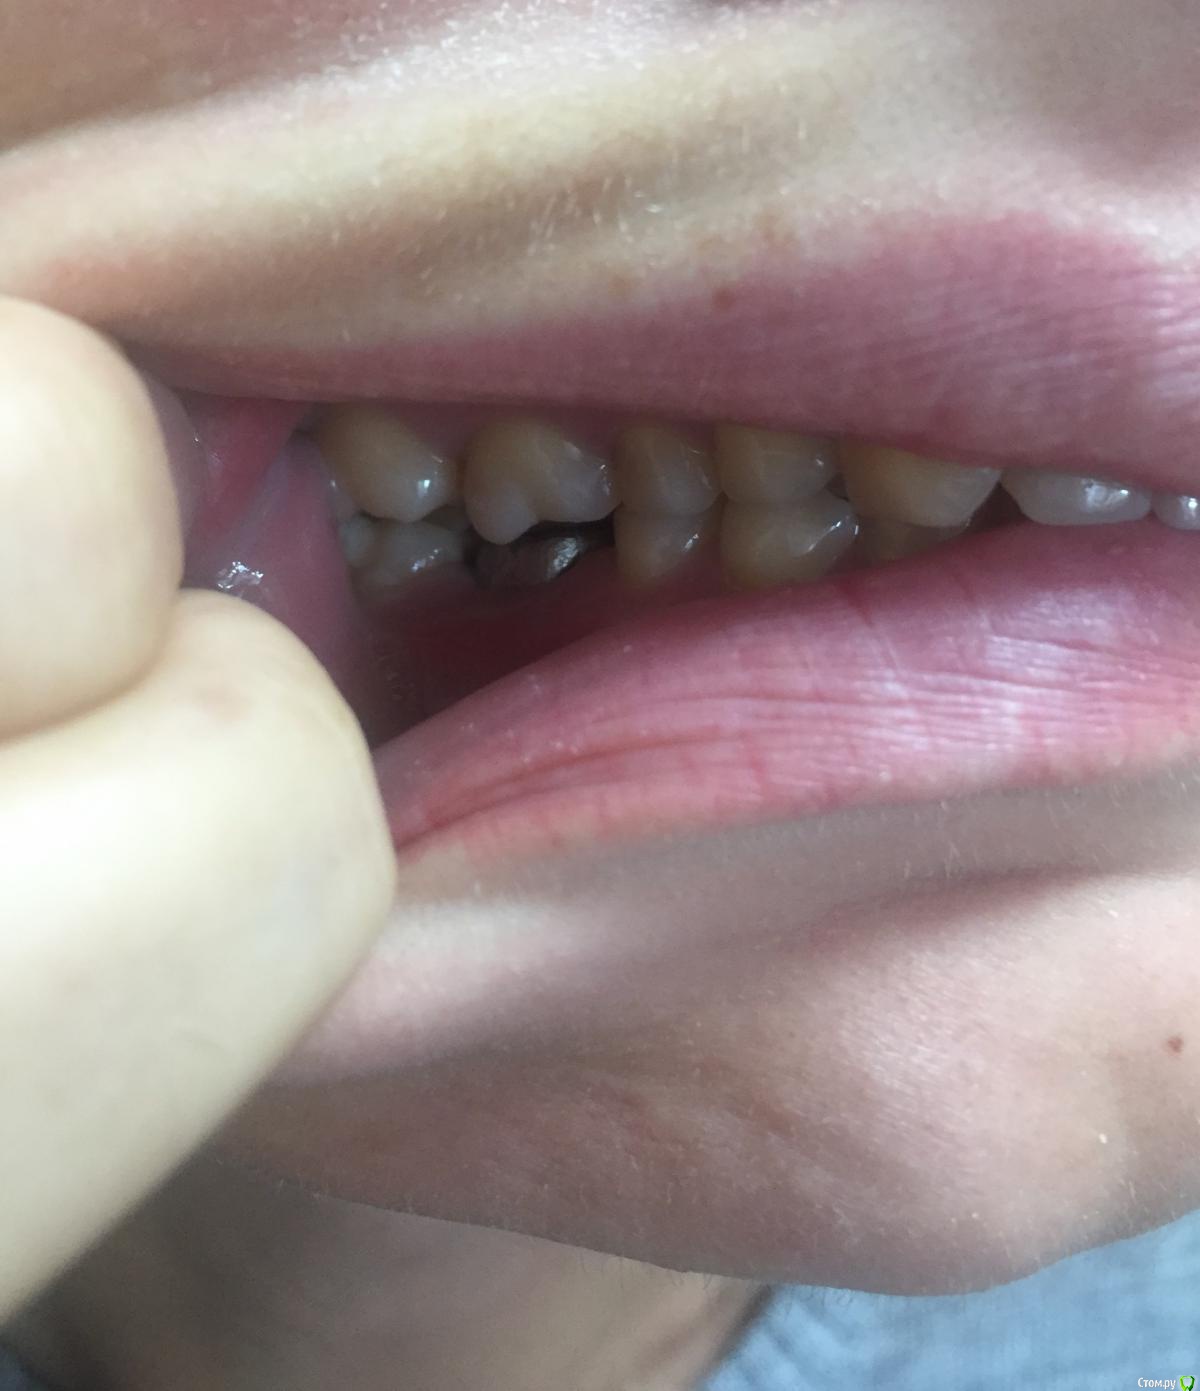

kramer Опубликовано 28 сентября, 2018 Поделиться Опубликовано 28 сентября, 2018 Нужно фото с сомкнутыми зубами 1 Ссылка на комментарий

Мария Сп Опубликовано 30 сентября, 2018 Автор Поделиться Опубликовано 30 сентября, 2018 Фото с сомкнутыми зубами направляю. Ссылка на комментарий

gum Опубликовано 2 октября, 2018 Поделиться Опубликовано 2 октября, 2018 Здравствуйте. Судя по данным фото у вас патологическая стираемость зубов и как мне кажется проблема с прикусом (нижние зубы наклонены язычно). Рекомендую установить пластмассовую коронку и сходить на консультацию к ортодонту. Ссылка на комментарий